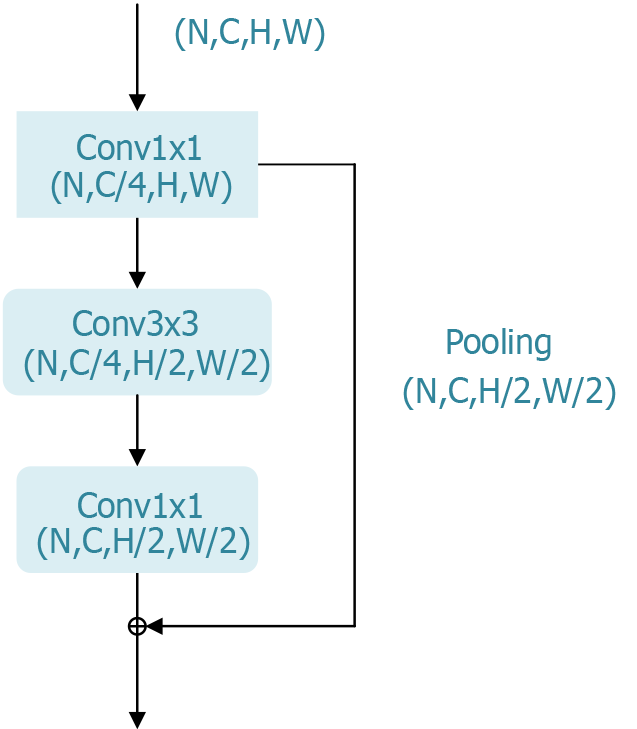

ResNet has achieved significant success in computer vision tasks such as image classification, object detection, and image segmentation and has become the foundational architecture for many subsequent deep learning models. Its outstanding performance in the ILSVRC 2015 competition further validated its effectiveness, making it a primary choice for evaluating the most suitable model for the early-stage classification of esophageal cancer in this study. To adapt ResNet for this specific application, we modified the network’s decoder structure from its original design for image classification to better suit esophageal cancer classification needs. The bottleneck block, a key component of ResNet’s residual module, is shown in Figure 3.